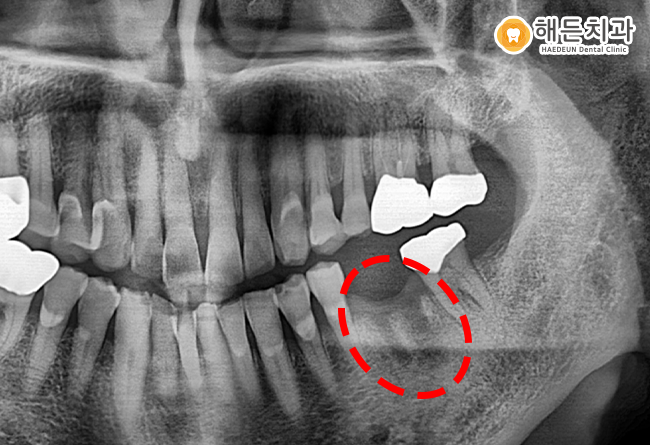

위의 사진과 같이 잇몸뼈가 제대로 만들어져 있고 임플란트 픽스처와 안정적으로 결합되었습니다.

따라서 해든치과에서는 사진뿐만 아니라 치조골과 잘 결합되었는지 수치로도 확인하는 과정을 거치고 있습니다.

환자분 또한 적정수치인 것을 확인하고 보철물과 픽스처를 이어주는 어버트먼트 또한 연결하여 크라운을 올려 마무리했습니다.